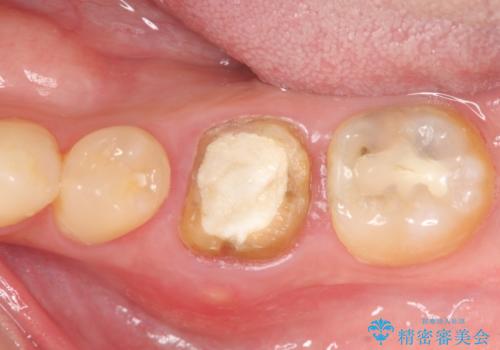

放置してしまった歯 根管治療からの機能回復

- 放置してしまった歯が痛み、いよいよ耐えられなくなり来院されました。

根管治療の途中で放置してしまっていた歯を、最終的に機能回復できるよう治療を行っていきます。

治療途中の歯の放置は、より虫歯を進行させてしまい抜歯に至ってしまうこともあるので注意が必要です。